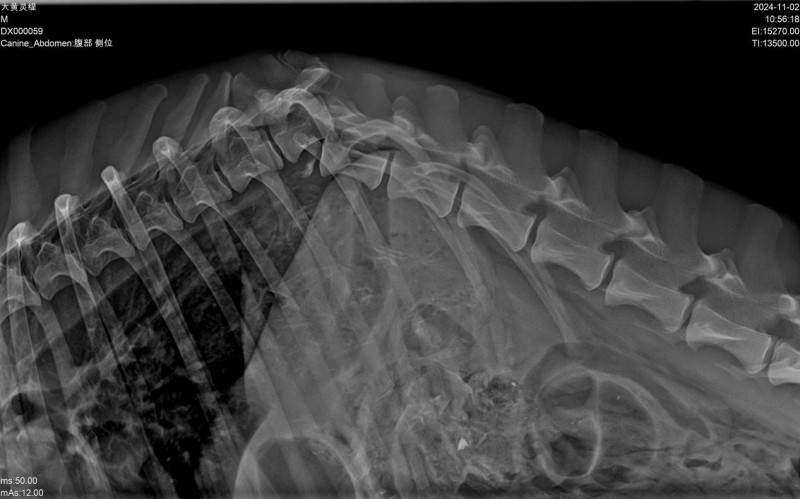

宠物诊疗中,“穿透不足”是大型宠、肥胖宠物成像的核心痛点——常规低压DR拍摄大型犬腰椎、骨盆等厚实部位时,射线难以穿透深层组织,导致图像模糊、骨骼轮廓不清,不得不反复镇静、重复拍摄,既耗时费力,又增加宠物应激反应与辐射累积风险。

必康32kW高压发生器可稳定输出高强度、高均匀度的X射线,凭借超强穿透能力,轻松适配全场景宠物体型需求:无论是藏獒、阿拉斯加等大型犬的厚实骨骼与肌肉组织,还是肥胖宠物的深层脏器,都能一次性穿透,精准捕捉病灶细节;针对猫咪、小型犬、鹦鹉等小型异宠,设备可精准调控射线能量,避免成像过曝,兼顾穿透性与细节捕捉力,真正实现“一次拍摄、一次成像合格”,大幅降低重复拍摄率,为宠医减负、为宠物护航。